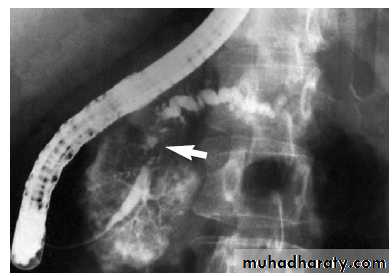

• ERCP : The most accurate test to determine the anatomy of the pancreatic duct.

ERCP: irregular stricture Ca pancreas

• ERCP:

• Barium meal: “ pad sign” which is widening of the C-shaped duodenal loop.

• The reversed 3 sign due to filling defect of the periampullary mass.